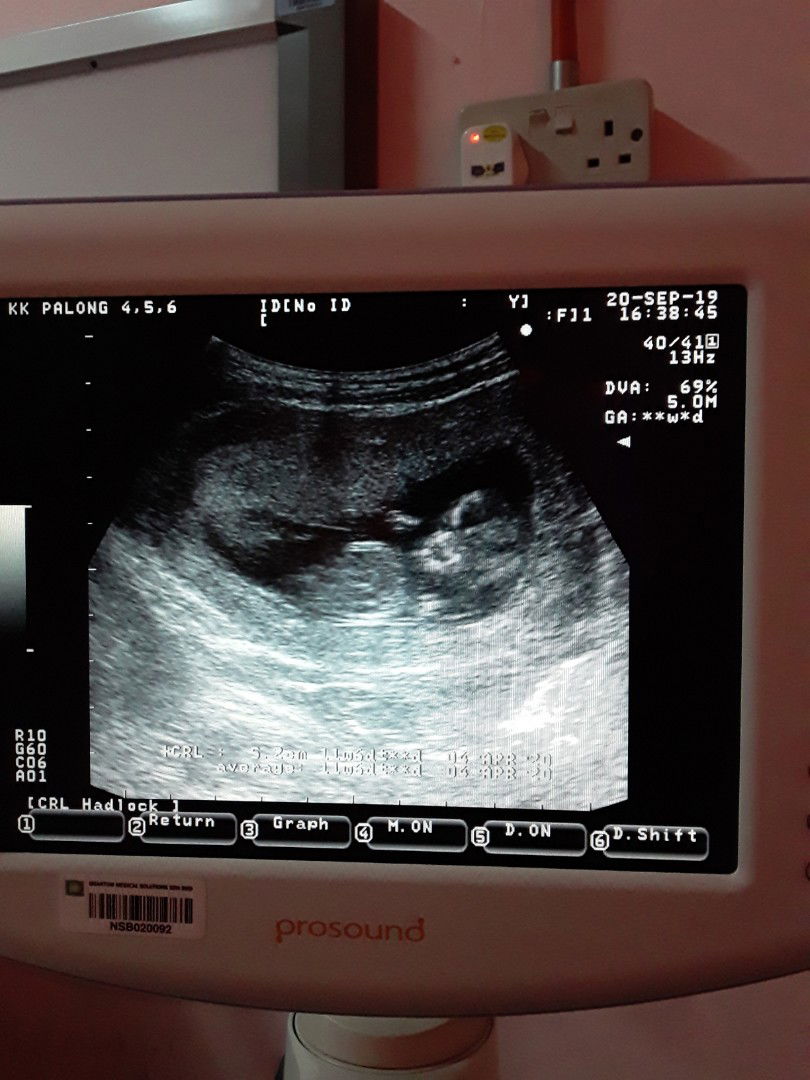

Hi. Sy dah berkahwin selama 7 tahun. Baru dapat tahu mengandung dan usia kandungan baru mencecah 5 minggu 5 hari. Mintak doa semua kandungan selamat. ?